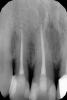

Marina_A Опубликовано 25 мая, 2013 Поделиться Опубликовано 25 мая, 2013 Пациентка обратилась с жалобами на постоянную ноющую боль в 11 зубе ( по ночам тоже) , боль при накусывании на протяжении нескольких дней и зуд между 11, 12. она связала это с тем что ее продуло) в общем, зуб мы депульпировали. в первое посещение помыла+ коласепт (боли прекратились), во второе запломбировала.через месяц она пришла и сказала что зуб болит уже несколько дней снова. Клиника такая же, как была до лечения. (перкуссия+, ноющие боли). В общем, если вкратце, она приходит каждый раз после того как ее продует, либо она промерзнет (бассейн, кондиционер...). За это время ( 6 мес) мы пробывали пить противовоспалительные, антибиотики, пришлифовывали,искали пропущенную анатомию, все безрезультатно. сейчас у нее постоянно болит при накусывании (не остро), и во время обострений ноющие боли присоединяются. почти 2 недели пациентка ходит с коласептом ( первые 4 дня после того как канал распломбировали боли прошли совсем), а потом все по кругу)я уже не знаю что с ней делать соседние зубы тоже жаждут лечения, но боли явно в 11.очень странно, но она постоянно жалуется на зуд между зубами 11 и 12. что это может быть? на кт ни перфу ни доп канал я не увидела. Ссылка на комментарий

ger_berra Опубликовано 25 мая, 2013 Поделиться Опубликовано 25 мая, 2013 (изменено) А недопак в 11 Вы не увидели? Коферр был?Если нет,то рот пац закрывал?На период "снимочка" или просто так? Изменено 25 мая, 2013 пользователем ger_berra Ссылка на комментарий

Marina_A Опубликовано 25 мая, 2013 Автор Поделиться Опубликовано 25 мая, 2013 А недопак в 11 Вы не увидели? нет, где? Ссылка на комментарий

ger_berra Опубликовано 25 мая, 2013 Поделиться Опубликовано 25 мая, 2013 нет, где?На последнем снимке. Ссылка на комментарий

Marina_A Опубликовано 25 мая, 2013 Автор Поделиться Опубликовано 25 мая, 2013 На последнем снимке.не вижу под недопаком Вы имеете в виду не до верхушки? все было с коффером и апекслокатором) Ссылка на комментарий

ger_berra Опубликовано 25 мая, 2013 Поделиться Опубликовано 25 мая, 2013 не вижу под недопаком Вы имеете в виду не до верхушки? все было с коффером и апекслокатором)Да,не до верхушки.У резцов верхней челюсти рентгенологический апекс почти совпадает с физиологическим. Ссылка на комментарий

ger_berra Опубликовано 26 мая, 2013 Поделиться Опубликовано 26 мая, 2013 Не нашла ни перелома, ни трещины.Со скопом смотрела, инстументом по стенкам канала прошлась, ниче не зацепила, болезнености не было) ger_berra что за ТС? Первый и второй снимок сделаны с разницей в 3 месяца.Ну недопак же!Латералка,верно?Сколько по времени мыли после экстракции пульпы?Озвучивали?Не пойму,что можно при трещине цепануть по стенке канала?Как считаете? Признак трещины-это узкий зубодесневой карман. Покажите,плиз, снимки всех этапов ретритмента. Ссылка на комментарий

Marina_A Опубликовано 26 мая, 2013 Автор Поделиться Опубликовано 26 мая, 2013 (изменено) Ну недопак же!Латералка,верно?Сколько по времени мыли после экстракции пульпы?Озвучивали?Не пойму,что можно при трещине цепануть по стенке канала?Как считаете? Признак трещины-это узкий зубодесневой карман. Покажите,плиз, снимки всех этапов ретритмента.Да, латералка. в первое посещение часа пол, я думаю. уз обработка была. при трещине болевых ощущений в месте самой трещины быть не может никаких разве? я сегодня кт пересмотрела, не знаю пока как выложить полностью, но неужели это доп канал???) Изменено 26 мая, 2013 пользователем M. Antoniuk 1 Ссылка на комментарий